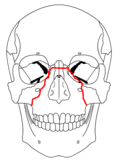

- Le Fort I fracture (horizontal), otherwise known as a floating palate, may result from a force of injury directed low on the maxillary alveolar rim, or upper dental row, in a downward direction. The key component of these fractures, in addition to pterygoid plate involvement, is involvement of the lateral bony margin of the nasal opening. They also involve the medial and lateral buttresses, or walls, of the maxillary sinus, traveling through the face just above the alveolar ridge of the upper dental row. At the midline, the inferior nasal septum is involved. Historically, it has also been referred to as a Guérin fracture, although this name is less commonly used in practice.

- Le Fort II fracture (pyramidal) may result from a blow to the lower or mid maxilla. The key component of these fractures beyond the pterygoid plate fractures is involvement of inferior orbital rim. When viewed from the front, the fracture is classically shaped like a pyramid. It extends from the nasal bridge at or below the nasofrontal suture through the superior medial wall of the maxilla, inferolaterally through the lacrimal bones which contain the tear ducts, and inferior orbital floor through or near the infraorbital foramen.